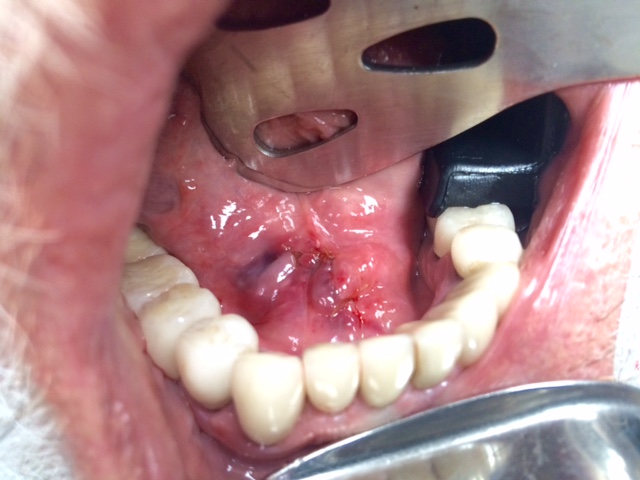

Head and Neck Tumor and Reconstruction

(cancer reconstruction)

Often after a patient has gone through various treatments for cancer there is a need that oral and maxillofacial services can provide for. In many cases, reconstructive surgery benefits patients having gone through specific skin cancers that are typically found in and around the head and neck regions. Depending on the severity and location of the cancer, skin cancer reconstruction options can range from simple to advanced procedures in order to restore both function and form.

The photos on this website are from real surgeries performed by Dr. Ulloa. Due to the

graphic nature of the images and content, viewer discretion is advised.